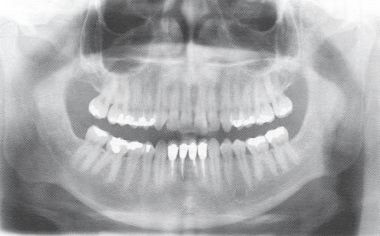

![]() |

| Maslow vajaduste püramiid. Foto: simplypsychology.com |